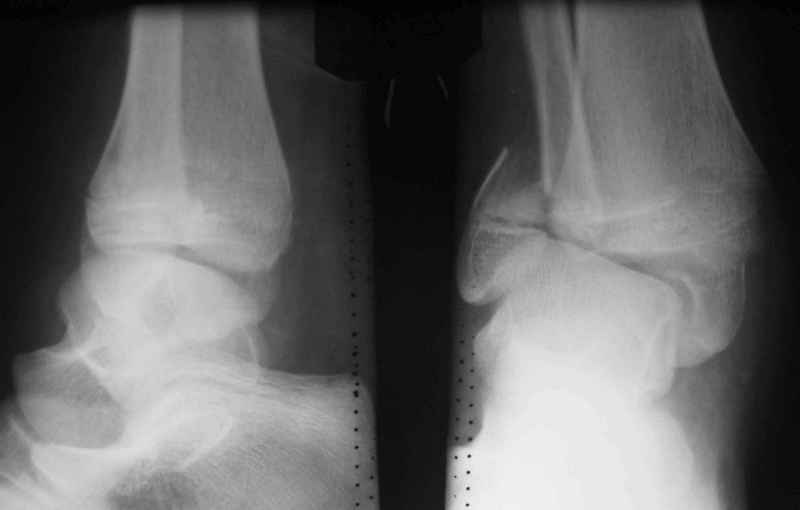

Здравствуйте, коллеги.Обратились родители мальчика 15 лет. Сами врачи.В июле 2009 года - перелом лодыжек.

Лечили спорно, на мой взгляд. В результате - - сращение наружной лодыжки с укорочением, подвывих голеностопа кнаружи (вальгус) в итоге компенсаторно передний отдел стопы ставит на варус. Нагрузку ограничивает.

Снимки в приложении.